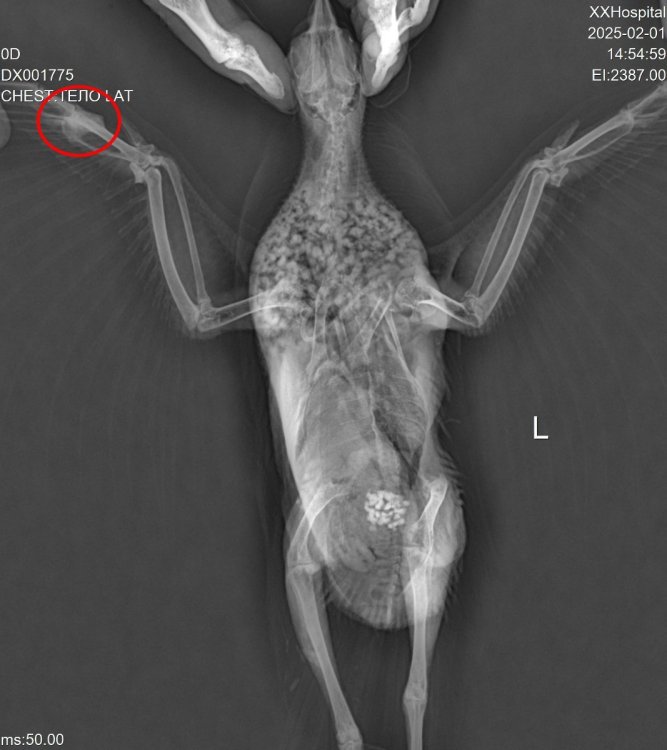

рентен нужно в двух проекциях сверху и сбоку и позвоночник и ноги и крыло

Вечер добрый! Мы наконец повторили рентген. @Zosia не могли бы взглянуть, пожалуйста?

DX001775_4.jpg

На снимке странно выглядит зона,где должен находиться коракоид. Возможно имеем его перелом. Если это так- то понятно отсутствие возможности летать и общая вялость,т.к. это чрезвычайно болезненный перелом и опасный...

Почему на правом крыле вы видите "шишку"- непонятно. Внешне сустав (локтевой) правого крыла без изменений.

Вообще все положение тела птицы несколько "скособочено" вправо... возможно был плоский удар (машина), и имеются отечные явления

,посттравматические.

Из-за несколько скривленного положения тела на латеральной проекции (праволатеральная) позвононик странно расположен, "фрагментарно", с S-образным изгибом.

Поэтому вопрос- птица какает нормально? Т.е. стандартно порциями, а не постоянным изливом фекалий?

Череп на ВД снимке без патологий.

На лат проекции есть некие объекты, в зоне гонад/яичника, больше похожие на гранулемы яичника .

Пока кроме продолжения терапии НПВС, миорелаксантами, витаминами В6 и В12, источниками кальция- нечего добавить (по части преджполагаемой травмы).

@Zosia Огромное спасибо!!! Какаем нормально, с этим проблем нет! Шишка у на здесь (отметила кружочком)

Он "бережет" правую лапу, если наступает, то на кулачек. Или держит на весу. На правой стоит нормально. Правое крыло тоже не рабочее. Иногда, если перенервничает, закидывает голову назад, вплоть до кувырков на спину. В спокойном состоянии голову держит ровно. Энтерофурил не пили. Приняла к сведению!